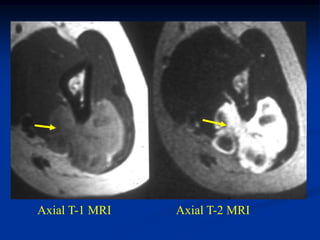

Case #1199

30 year male with

myxoid liposarcoma

posterior thigh

Sagittal T-1 MRI

Sagittal T-2 MRI

tumor

Axial T-1 MRI

Axial Gad contrast MRI

Coronal Gad

contrast MRI

Surgical specimen

Photomic